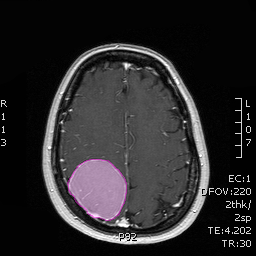

Διάγνωση Απαραίτητα είναι: Η λεπτομερής λήψη ιστορικού και η κλινική εξέταση, Η μαγνητική τομογραφία του εγκεφάλου με σκιαγραφικό, Σε ορισμένες περιπτώσεις: Η μαγνητική αγγειογραφία ή/και φλεβογραφία του εγκεφάλου, Η μαγνητική τομογραφία του εγκεφάλου με σκιαγραφικό για νευροπλοήγηση, Ηλεκτροεγκεφαλογράφημα και άλλες εξειδικευμένες εξετάσεις όπως μέτρηση οπτικής οξύτητας και οπτικών πεδίων προτείνονται κατά περίπτωση. |